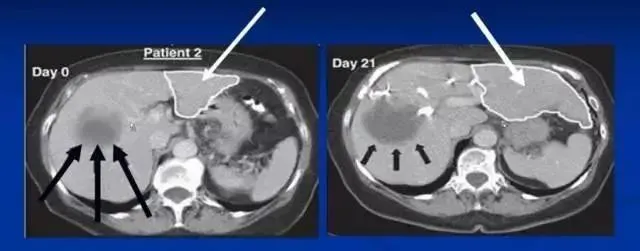

沈陽軍區總醫院消化內科郭曉鐘等經股動脈肝內自體骨髓干細胞移植治療肝硬化102例報告。

術后復查提示:

血漿蛋白改善在各項指標中最顯著,其次為凝血功能的改善,可改善肝臟合成蛋白功能,對目前肝硬化腹水的患者具有積極意義。